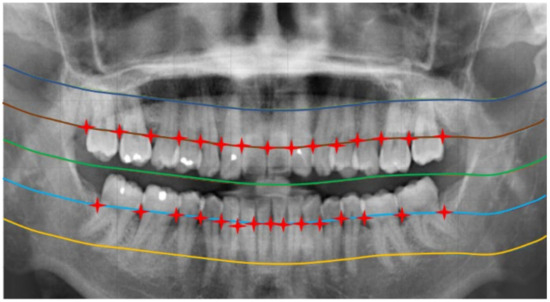

2.2. Image Segmentation

2.2.1. Curve of the Mouth

2.2.2. Curve Adjustment

2.2.3. Positioning Numbers